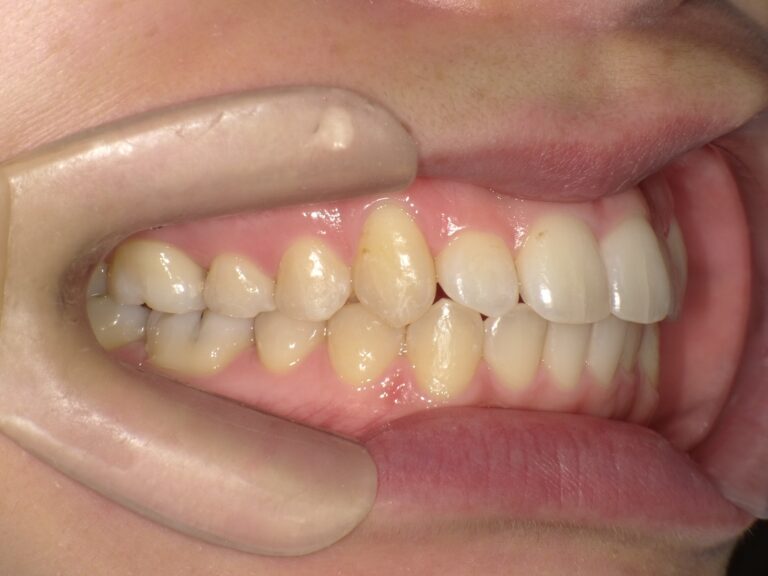

症例2:八重歯が気になる

| 患者様データ | 20代 女性 |

| 来院主訴 | 八重歯が気になる。 |

| 治療内容 | 八重歯を治すために上の親知らずを抜歯し、インビザラインにてマウスピース矯正を開始しました。かみ合わせを整えるためにゴムかけを行いました。 |

| 概算治療費 | 約85万円 |

| 治療期間 | 1年3ヶ月 |

| 通院回数 | 8回 |